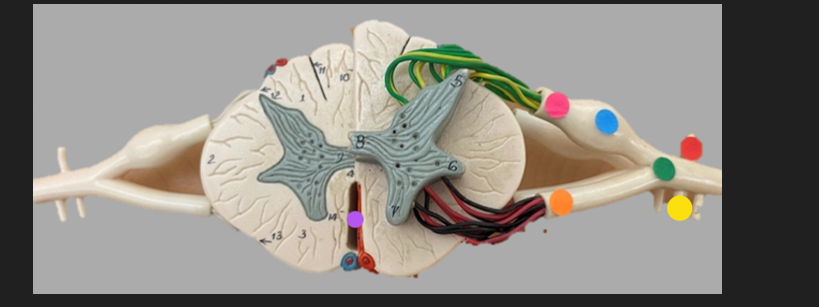

green dot

spinal nerve

orange dot

ventral root

pink dot

dorsal root

blue dot

dorsal root ganglion

red dot

dorsal ramus

yellow dot

ventral ramus

purple dot

anterior median fissure

red dot

posterior (dorsal) horn

purple dot

lateral horn

dark blue dot

anterior (ventral) horn

orange dot

dorsal column

yellow dot

lateral column

dark green

anterior column

line green and pink doit

gray commissure

light blue dot

posterior median sulcus